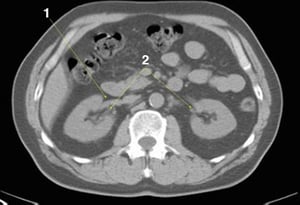

CT-Scan von Abdomen und Becken mit normaler Anatomie ohne Kontrastmittel (Folie 13)

1 = V. mesenterica superior; 2 = A. mesenterica superior.

© Springer Science+Business Media